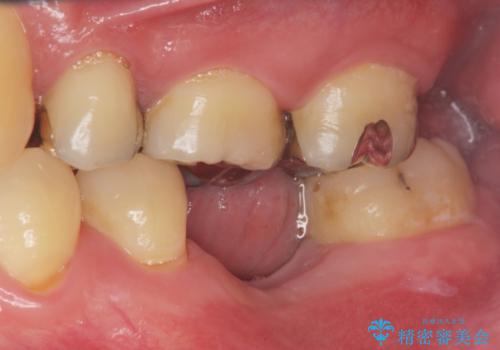

- 「長年虫歯放置した結果、抜歯となってしまった左下奥歯に歯を入れたい」、と希望され来院されました。

前後の歯は虫歯も治療歴もないため、前後の歯を削らなくてはいけないブリッジではなくインプラント治療による咬合機能回復を計画します。